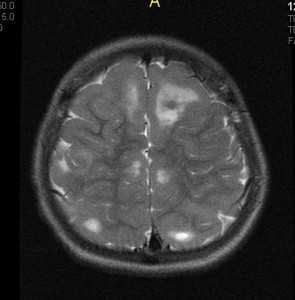

Для детей раннего возраста, на еще незавершенных процессов миелинизации наиболее типичными изменили является линейные очаги на Т2ВИ выявляемые по ходу миграционных путей больших полушарий головного мозга. Эти изменения могут сочетаться с кортикальными и субкортикальными очагами ( туберами ), так и быть единственным проявлениям при МРТ исследовании. Наличие кортикальных и субкортикальных туберов типично для всех возрастных групп пациентов. В их проекции могут формироваться кисты, так же они могут быть частично или полностью кальцинированы. Их размеры и количество варьируется индивидуально для каждого больного.

Наиболее типичная локализация большие полушария головного мозга, однако у 15% пациентов туберы могут располагаться в мозжечке. Туберы представляют собой глионейрональные гамартомы и состоят из дезорганизованной клеточной ткани белого вещества.

При подозрении на эту болезнь обязательно следует проводить МРТ головного мозга. При этом в головном мозге выявляются характерные МРТ-признаки туберозного склероза: корковые и подкорковые узлы (туберсы), субэпендимальные узелки (гамартомы), а также различные изменения белого вещества - очаговые и кистозные.